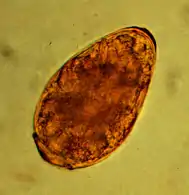

The approximately 85 µm large egg of toxocara mystax in the microscopic image.

The most common roundworm in most cats is toxocara mystax (syn. toxocara cati), infestation with toxascaris leonina is less common. Only in ocelots in Texas was T. leonina detectable in every animal, making it the most common parasite,[2] and in bobcats in Nebraska it was observed almost as often as T. mystax.[3] Both species of roundworm occur worldwide and roundworm infestation is a very common endoparasitosis. The adult roundworms, up to 10 cm long, live in the small intestine. The female worms produce a large number of eggs, which are released into the environment with the feces. The infective larvae develop in the eggs after about four weeks.

In the case of worms in vomit, the diagnosis can already be made without special examinations. A roundworm infestation can be detected with relative certainty by microscopic detection of the eggs extracted from the feces using the flotation method.